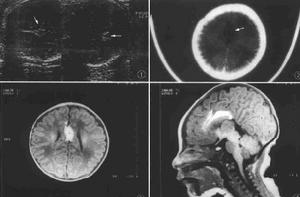

彎曲菌也可引起腸道外感染,故有彎曲菌病之稱。腸道外感染多見於35-70歲的患者或免疫功能低下者。常見症狀是發熱、咽痛、乾咳、蕁麻疹、頸淋巴結腫大或肝脾腫大,黃疸及神經症狀。部分血行感染,發生敗血症、血栓性靜脈炎、心內膜炎、心包炎、肺炎、膿胸、肺膿腫、腹膜炎、肝膿腫、膽囊炎、關節炎及泌尿系感染。少數還可發生腦血管意外,蛛網膜下腔出血、腦膜腦炎、腦膿腫、腦脊液呈化膿性改變。孕婦感染者常見上呼吸道症狀、肺炎及菌血症。可引起早產、死胎或新生兒敗血症及新生兒及新生兒腦膜炎。病死率不高,老年人偶可發生。